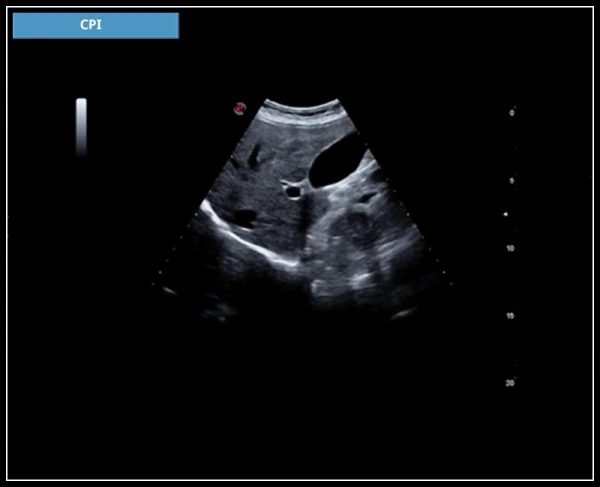

CPI: CPI – это комбинация низкочастотной и высокочастотной модуляции, обеспечивающая уверенную диагностику для каждого пациента с оптимальным разрешением и лучшим проникновением.